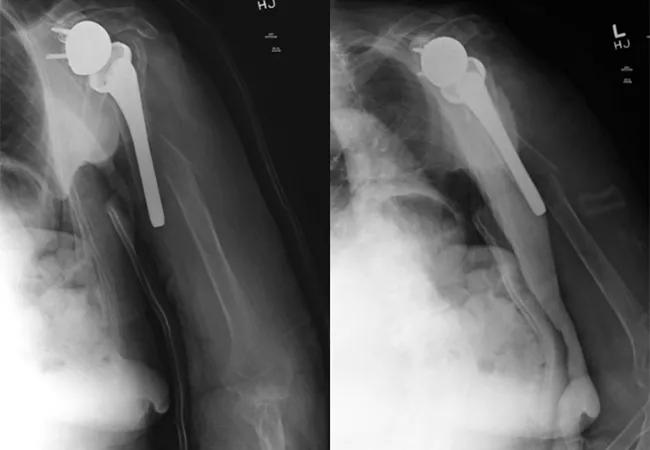

An 84-year-old right-hand-dominant female fell onto her left arm from a standing height four days prior to presentation. She lived at home with her family and used a walker for ambulation doing basic activities of daily living. She went to the local emergency room and was diagnosed with a left periprosthetic humerus fracture around a reverse total shoulder replacement done more than five years earlier for rotator cuff tear arthropathy (Figure 1). Prior to the fall, she had shoulder-level function with her reverse replacement and no complications or difficulties. Her exam in the office showed intact motor function. Her axillary nerve and deltoid appeared to be functioning, and her prior deltopectoral incision was well healed. Surgical intervention was discussed due to the displacement and comminution of the fracture.

Figure 1. Injury films showing comminuted periprosthetic humerus fracture around a reverse shoulder replacement stem.